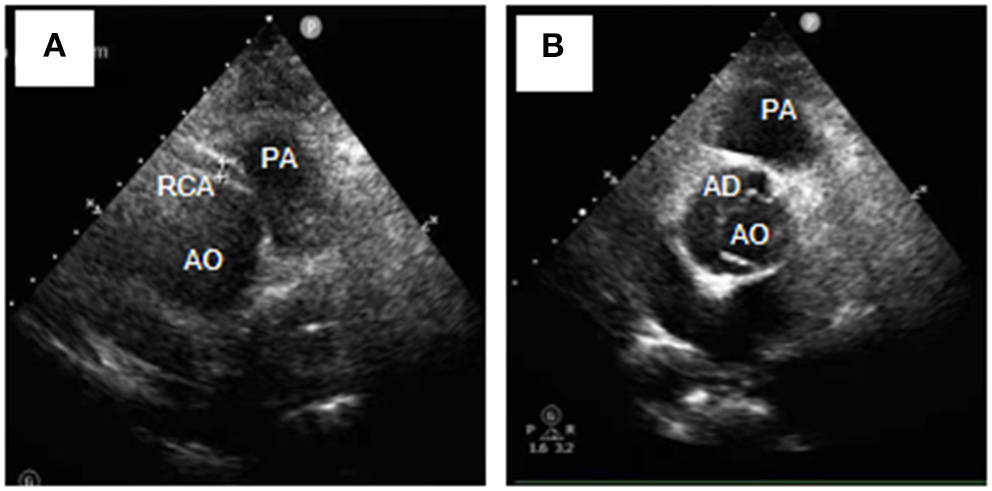

A 54-year-old female was admitted urgently again because of sudden chest and back pain. At her first admission in June 2020, due to chronic atypical chest pain with paroxysmal syncope without any history, she was diagnosed with AAORCA and slight coronary stenosis (Figures 1A,B; Supplementary Video 1) after trans-radial coronary angiography and recovered after 2-week symptomatic treatment with medicine. At this time, no positive signs were found except a blood pressure of 162/90 mmHg at resting conditions and a slight diastolic murmur. An electrocardiogram (ECG) showed the mild ST-segment depression and cardiac troponin I was 0.17 ng/ml. Transthoracic echocardiography showed a Stanford type A aortic dissection (AD) with the widening from the aortic sinus to the thoracic aorta, avulsion injury at the opening of the right coronary artery (RCA), and the RCA originated from the left coronary sinus (LCS) (Figures 2A,B). Total aorta plus coronary CTA clarified the Stanford type A AD involving from the aortic root to the abdominal aorta, while left and right coronary arteries originated from the LCS (Figures 3A–C; Supplementary Video 2). The RCA was abnormally distributed and walked between the aorta-pulmonary artery (Figure 3D; Supplementary Video 3). Considering the risk of dissection rupture and SCD, an emergency surgery of aortic replacement and coronary anomaly correction was performed successfully for the patient. The AAORCA with AAD was identified and the aortic valves and LCS were still normal. We repaired the AAD with ascending aorta and total arch replacement combined with stent-graft elephant trunk technique, and corrected AAORCA with a right coronary artery bypass grafting. Postoperatively, the patient recovered well with medicine therapy including aspirin and clopidogrel, and was discharged on the 9th day after the operation. The patient is well now and has no limitations in daily activities at her 4-month follow-up visit.

Figure 2. Transthoracic echocardiography (Short-axis view at the great artery) revealed Stanford type A aortic dissection (A), avulsion of the RCA, and the RCA originating from the left coronary sinus (B). RCA, right coronary artery; AD, aortic dissection; AO, aortic; PA, pulmonary artery.